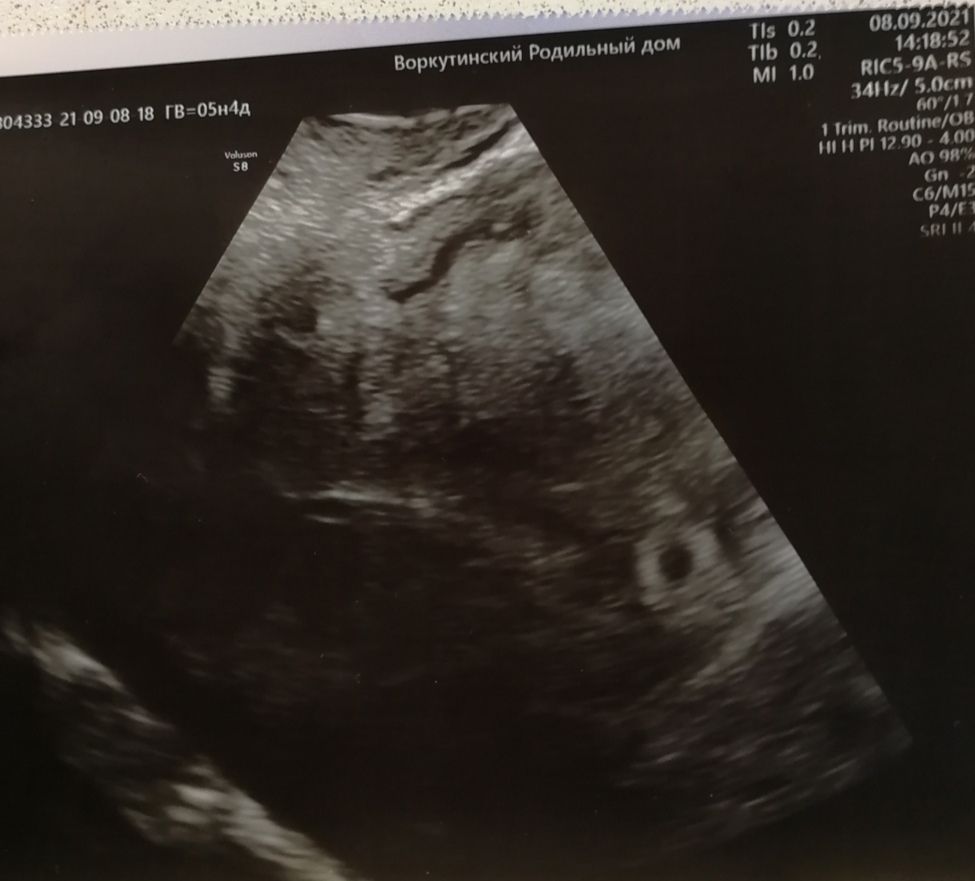

Девочки всем привет! Помогите пожалуй у моего мужа есть друг. Ему его девушка прислала фото узи и поздравляет что беременна. Я сама планирую беременность уже 10 лет но ТАКУЮ "беременность " первый раз вижу!

Подскажите реально ли это беременность или что это может быть??? Само узи с заключением она не показывает

Там есть вроде чёрный кружочек небольшой, похож на плодное яйцо. Но эмбриона пока не видно.

Фрау Макыздя, вот именно пятно на котором стоит измерение размера мне кажется никак не похож на плотное яйцо

Galina, вот то, которое с размерами, хрен знает вообще что это. Но выше от него чёрное пятнышко, оно похоже на плодное яйцо на 4-5 неделях.

Не вижу никакой Б, что то другое измерено, вообще на яичник похоже с фолликами и какими то включениями 🤷♀️

Просто со своим УЗИ сравниваю

Так выглядит плодное яйцо на очень маленьком сроке 4недели .

Вот так выглядит плодное яйцо. Так что думаю тут обман

Да, похоже на плодное яйцо. Ранний срок совсем

Matimacheha, разве плодное яйцо можеть иметь такую эхогенность что выглядит как пятно? Честно, я поэтому в недоумении потому что весь инет узи раннего срока перешарила но такое вижу такое впервые среди кучи узи плодного яйца раннего срока такого пятна ни разу не встречала🤔🤔🤔🤔

Больше похоже на полость или очаги эндометриоза, аденомиоза. Фолликул и жт внутри полые (чёрные цветом), рваные края.

Есть маленькие чёрные точки, похожие на фолликулы. Поэтому это яичник скорее всего, а не плодное яйцо.

Похоже на измерение эндометрия